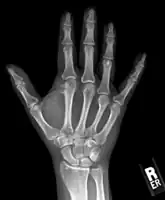

Medical imaging usually shows a well-defined wide-based bony growth on the surface of bone.[5] It can be pedunculated and irregular, giving it a "bizarre" appearance, and is not connected to underlying bone.[2]

X-ray hand, BPOP 2nd metacarpal -

X-ray hand, BPOP 2nd metacarpal (side view)